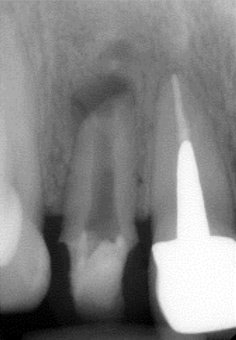

白丸で囲んでる付近に症状があり、ひどい時には目の付近まで腫れ上がってる感じがしたそうですが、口腔内には目立った症状はありません。

ちなみに今まで、この歯で3回も治療をしていました。しかし、症状は一向に改善していませんでした。

白丸で囲んだ部分が原因であるにも関わらず、レントゲンでは異常をきたす所見はありません。